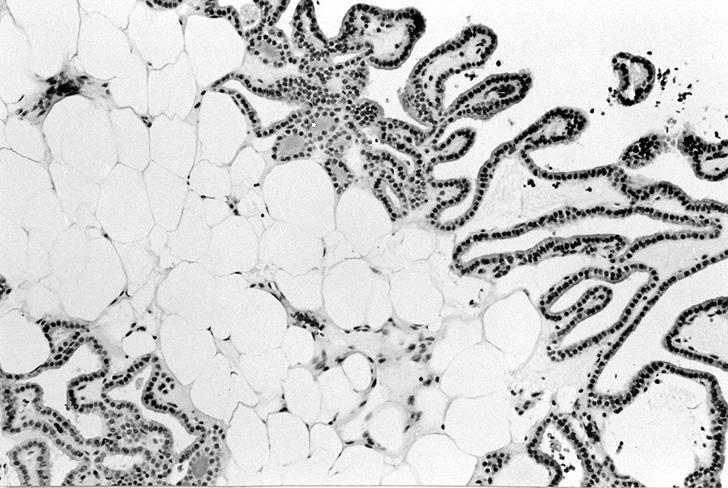

Microscopic (histologic) images

Contributed by Shipra Agarwal, M.D., Andrey Bychkov, M.D., Ph.D., Mark R. Wick, M.D., Asmaa Gaber Abdou, M.D. and AFIP

Patterns:

Atypical adenomas:

Microscopic (histologic) description

- Lipoadenoma: adipocytic metaplasia of the follicular adenoma